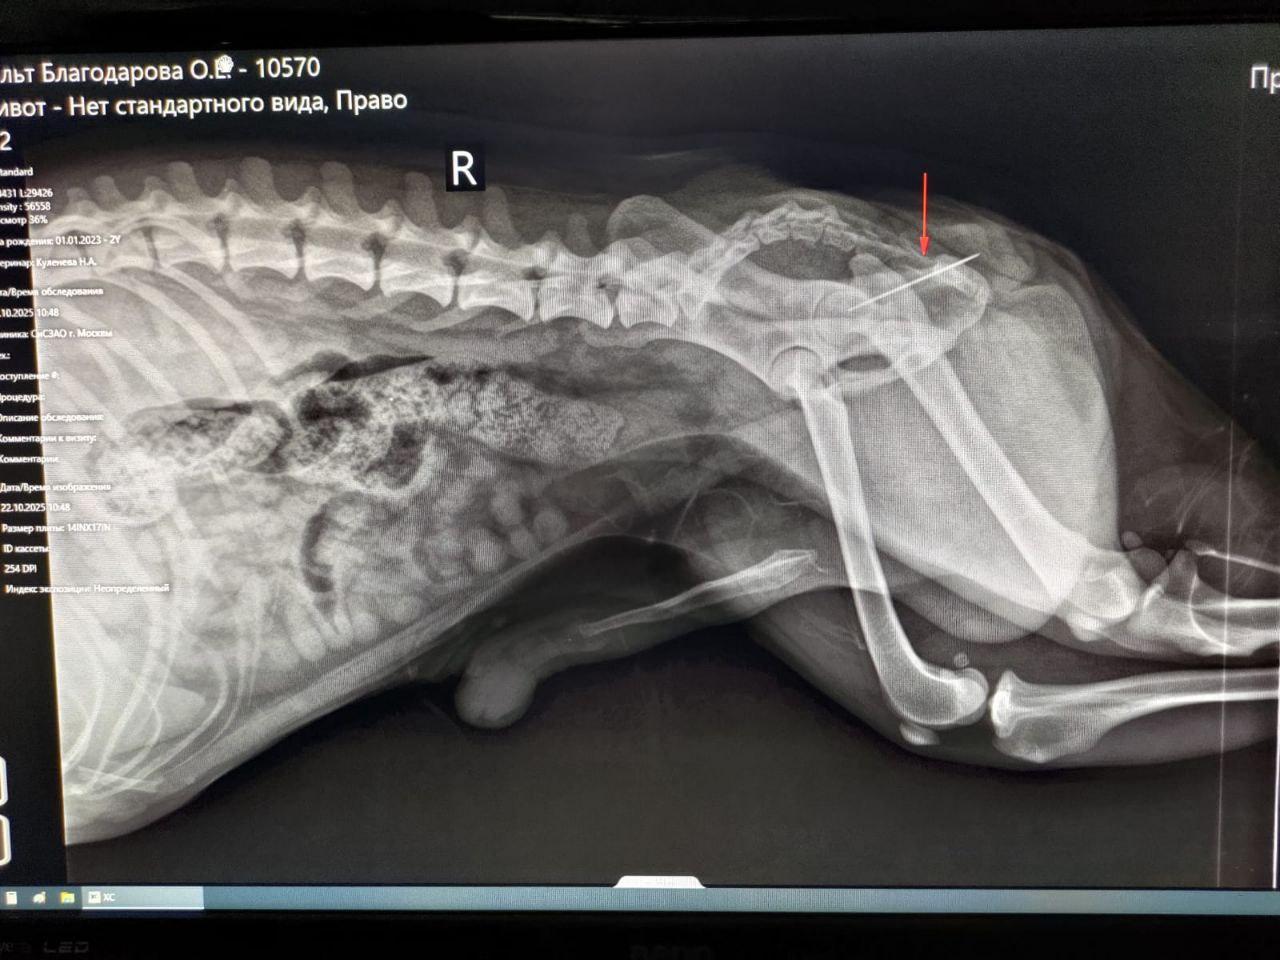

Собаку отправили на рентген. Исследование показало, что на другом конце нитки была иголка, которая застряла в прямой кишке.